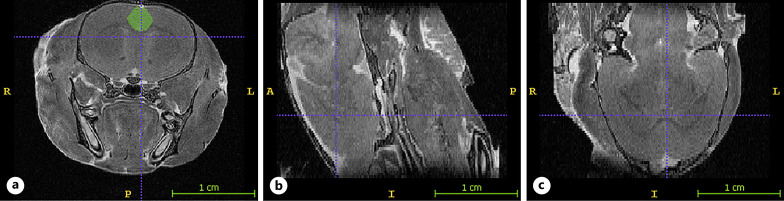

Method: Regional volumes were obtained via magnetic resonance imaging at either postnatal day 28 or postnatal day 40 (P40), which correspond to early and late adolescence, respectively.

Results: Consistent with prior research, VPA animals had reduced total brain volume compared to control animals. A novel outcome was that VPA animals had overgrown right hippocampi at P40. Differences in the pattern of development of the anterior cingulate cortex were also observed in VPA animals. Differences for the posterior cingulate were only observed in males, but not females.